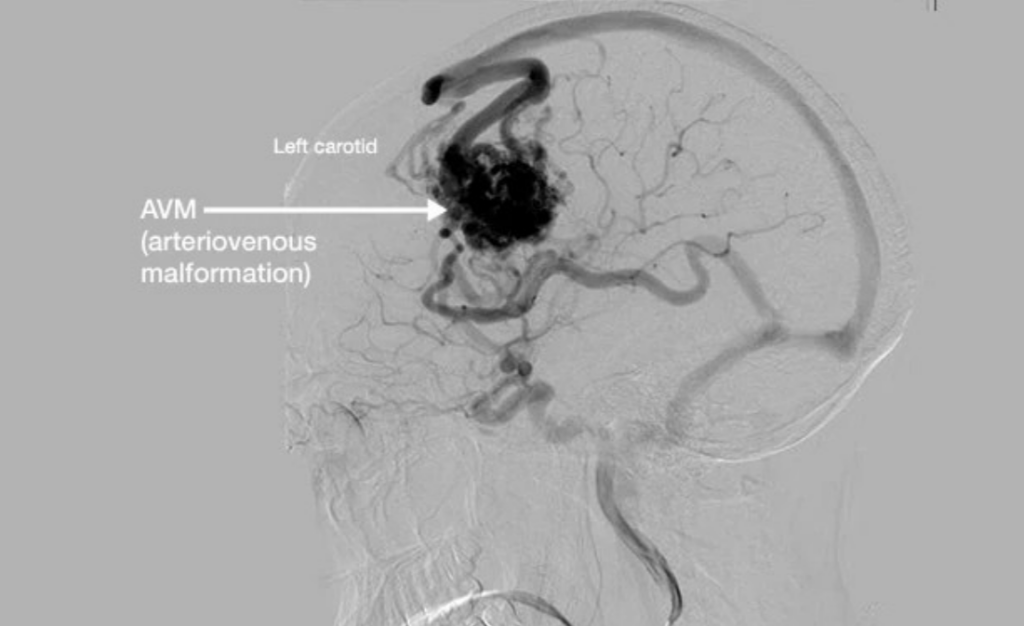

A Brain AVM (Arteriovenous Malformation) is an abnormal tangle of arteries and veins in the brain where blood flows directly from arteries to veins without passing through normal capillaries. This creates high-pressure flow that can weaken vessels over time.

AVMs are often diagnosed through MRI, CT scan, or Digital Subtraction Angiography (DSA), which provides a detailed roadmap of abnormal vessels.